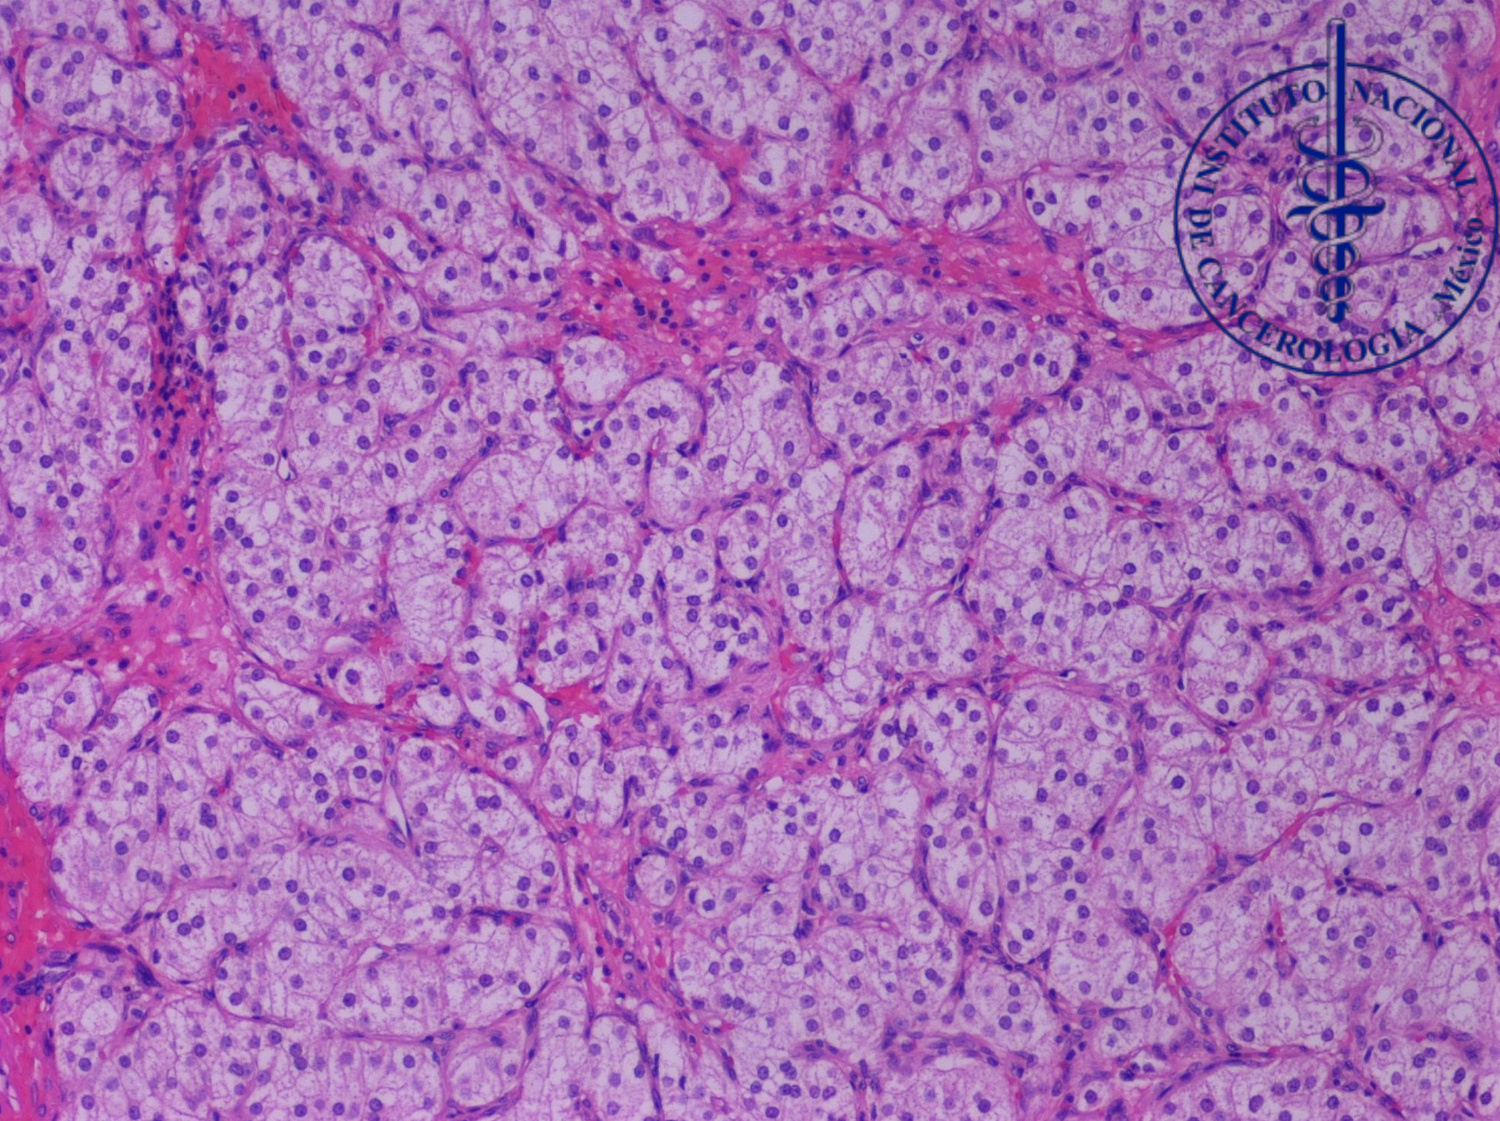

1.¿Con base en el cuadro clínico y los hallazgos histopatológicos, cual sería su diagnóstico?

A. Tumor de células esteroideas

B. Tumor de células de Sertoli

C. Metástasis de carcinoma renal de células claras

D. Carcinoma de células claras del ovario

3.¿Qué perfil de inmunohistoquímica, favorece el diagnóstico?

A. Inhibina +, Calretinina +, CD56 +, WT1+, Melan-A -, PAX8-.

B. Inhibina +, Calretinina +, SF1+, PAX8-, WT1-

C. PAX8+, CAIX+, CD10+, Inhibina-, Calretinina-.

D. Napsina+, PAX8+, CK7+, RE-, WT1-.